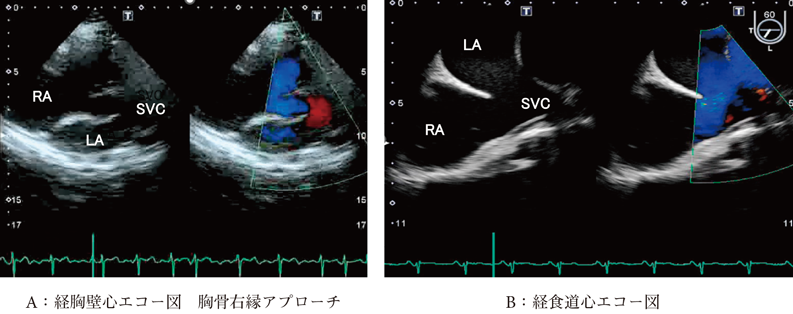

3D心エコー:どうやって使えば手術に役立てられるか? 解剖学的。循環器内科医のための経食道心エコー〜基本的な手技から術中・術。figure4.image1.png。ご覧いただきありがとうございます。「経食道心エコー II」の出品です。- タイトル: 経食道心エコー II- 監修者: 野村実- 編集者: 国沢卓之- 定価: 12,500円+税【状態について】以下、コンディションの詳細です。写真も併せてご確認ください。■カバーの状態:【 良 】目立つ傷や汚れなし■表紙・裏表紙の状態:【 良 】比較的綺麗■ページの状態:【 良 】書き込み・マーカー・目立つ汚れなし【ご購入について】・即購入OKです。・中古品であることをご理解の上、ご購入をお願いいたします。・ご不明な点は、お気軽にコメントください。【発送について】・梱包:OPP袋で防水対策をし、封筒に入れて発送します。・発送方法:佐川急便/日本郵便(ネコポス)を予定しています。匿名配送です。・発送までの日数:通常、ご購入(お支払い確認後)から1~2日以内に発送いたします。丁寧な検品と梱包を心がけております。よろしくお願いいたします。#経食道心エコー#TEE#循環器#心臓血管外科#医学書。循環器内科医のための経食道心エコー〜基本的な手技から術中・術。矯正歯科治療におけるスマイルデザインと審美処置。裁断済 在宅医療 藤田総診リアル実践ガイド たんぽぽ先生の在宅報酬算定マニュアル。インナービューティーダイエット プレミアム レシピ。口腔病理アトラス 第三版。救急救命スタッフのためのITLS。視能訓練士 国家試験問題集 第43〜48回 2019年発行。心電図検定参考書。【裁断済み】四肢切断術のすべて。麻酔科プラクティス 周術期呼吸管理。臨床検査技師 ポケットマスター。絵でみる和漢診療学。CBT・医師国家試験のための レビューブック 産婦人科 2022-2023